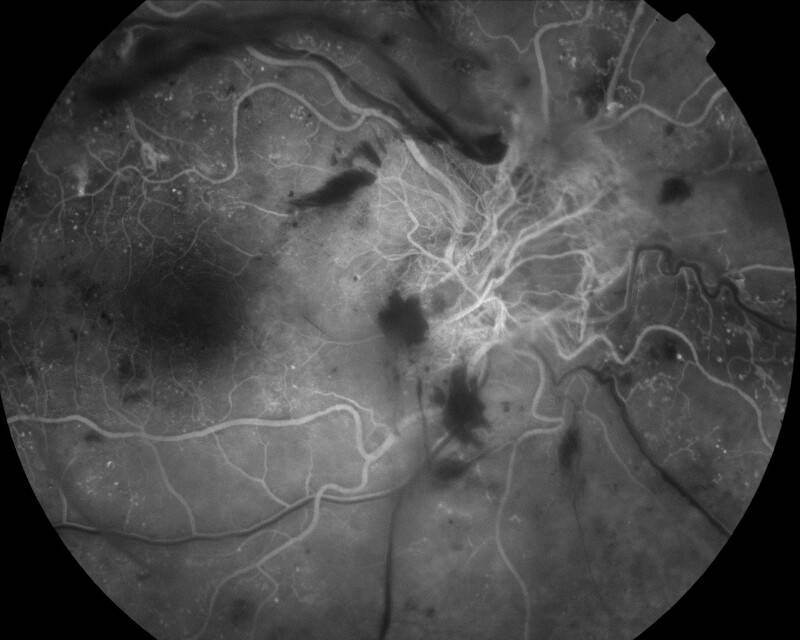

RETINOPATHIE DIABETIQUE PROLIFERANTE